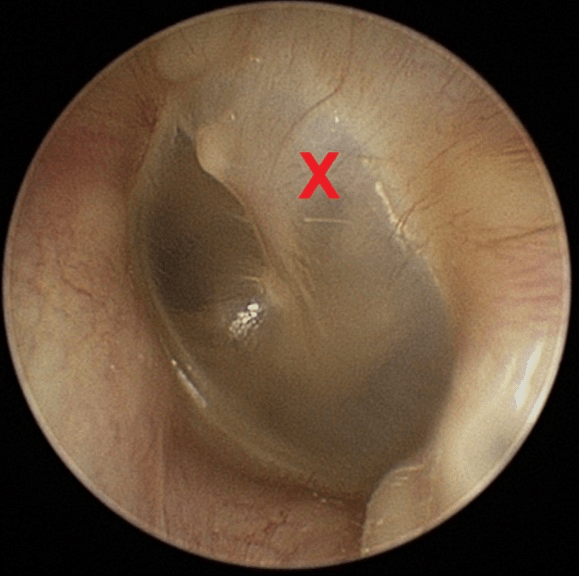

Nennen Sie Seite (links/rechts) und Quadrant der Markierung auf dem Trommelfell!

Linke Seite, Quadrant IV